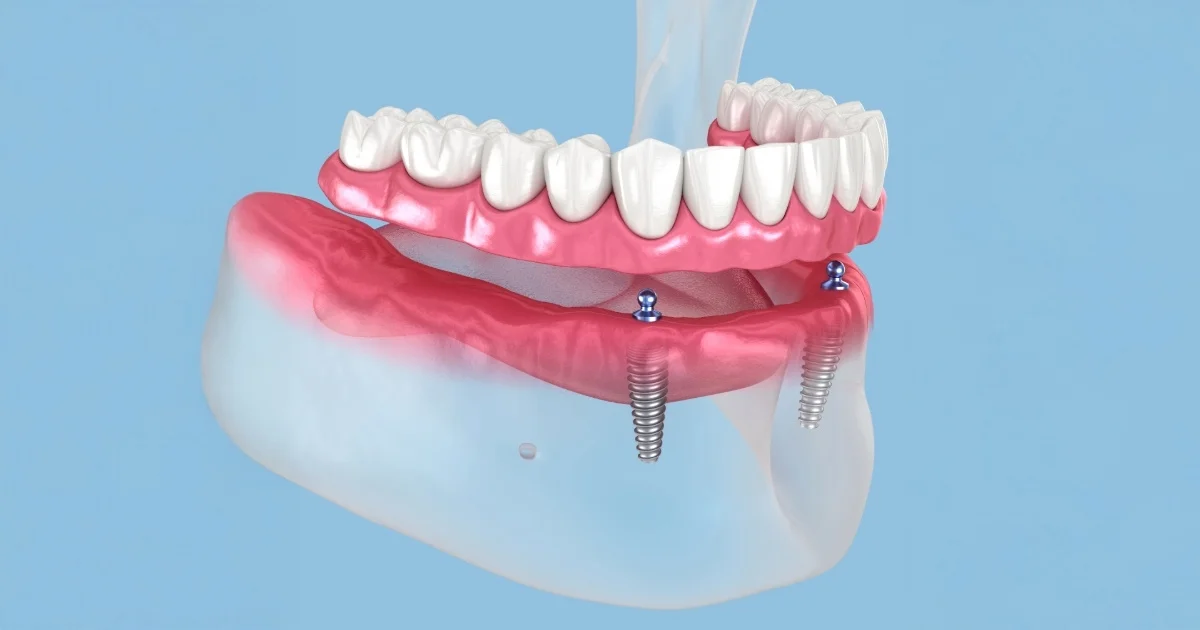

For patients who need to replace all teeth in one or both arches, we offer advanced full mouth implants in Detroit, MI. These include:

- All-on-4 dental implants.

- All-on-6 or full arch dental implants.

- Removable or fixed implant-supported dentures.

This life-changing procedure can restore chewing power, facial balance, and self-esteem—without the discomfort of traditional dentures.

Need teeth now? All Michigan Implants’ same-day dental implants Detroit service lets patients walk out with a brand-new smile in a single visit. Using immediate-load implant techniques, we ensure that your temporary prosthesis is stable, functional, and esthetically pleasing—on the same day as your implant placement.